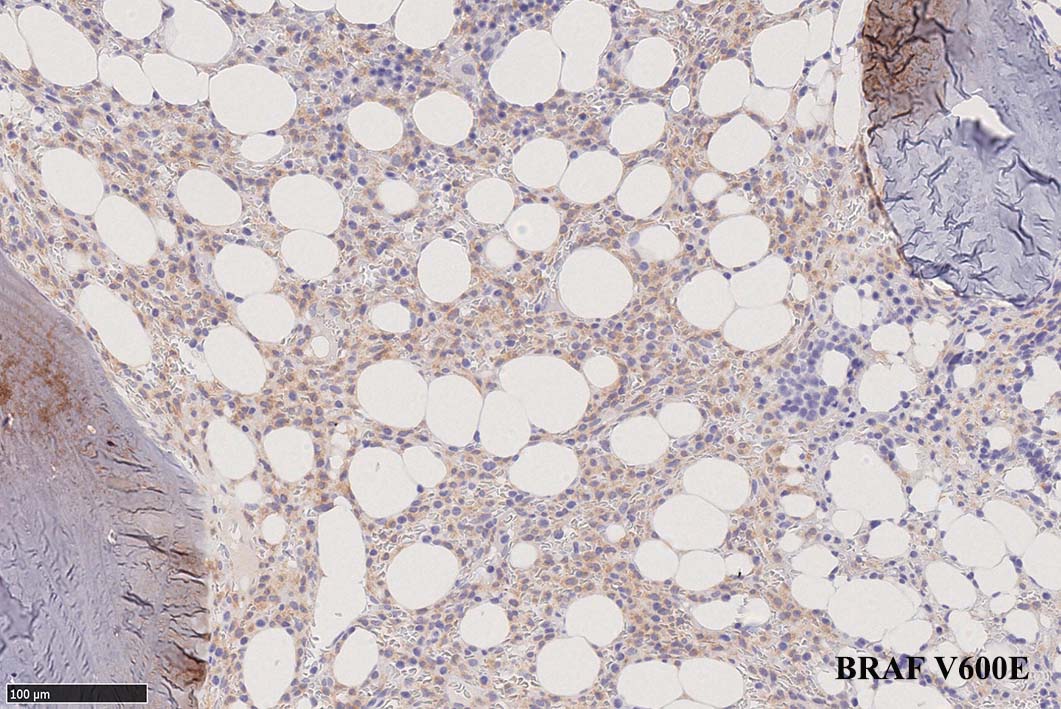

BRAF V600E変異タンパクの免疫染色(山梨医大 大石先生に染色していただきました. ベンタナ, Optiview)

Pathological Diagnosis: Hariy cell leukaemia